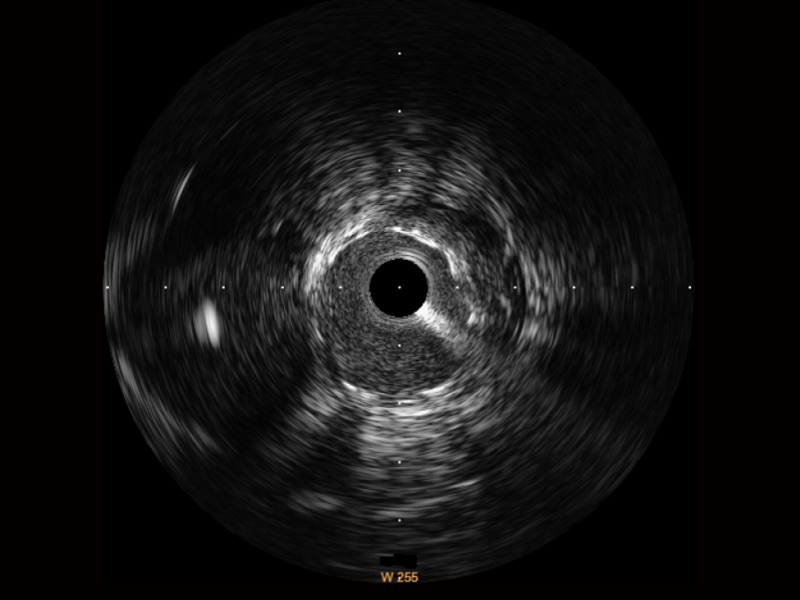

• 传统IVUS图像

对比传统IVUS导管成像,米兰官方网站宽频IVUS图像的近场支架梁显影更细腻,远场中膜外血管仍清晰可辨,兼顾远中近,兼顾分辨力与穿透深度